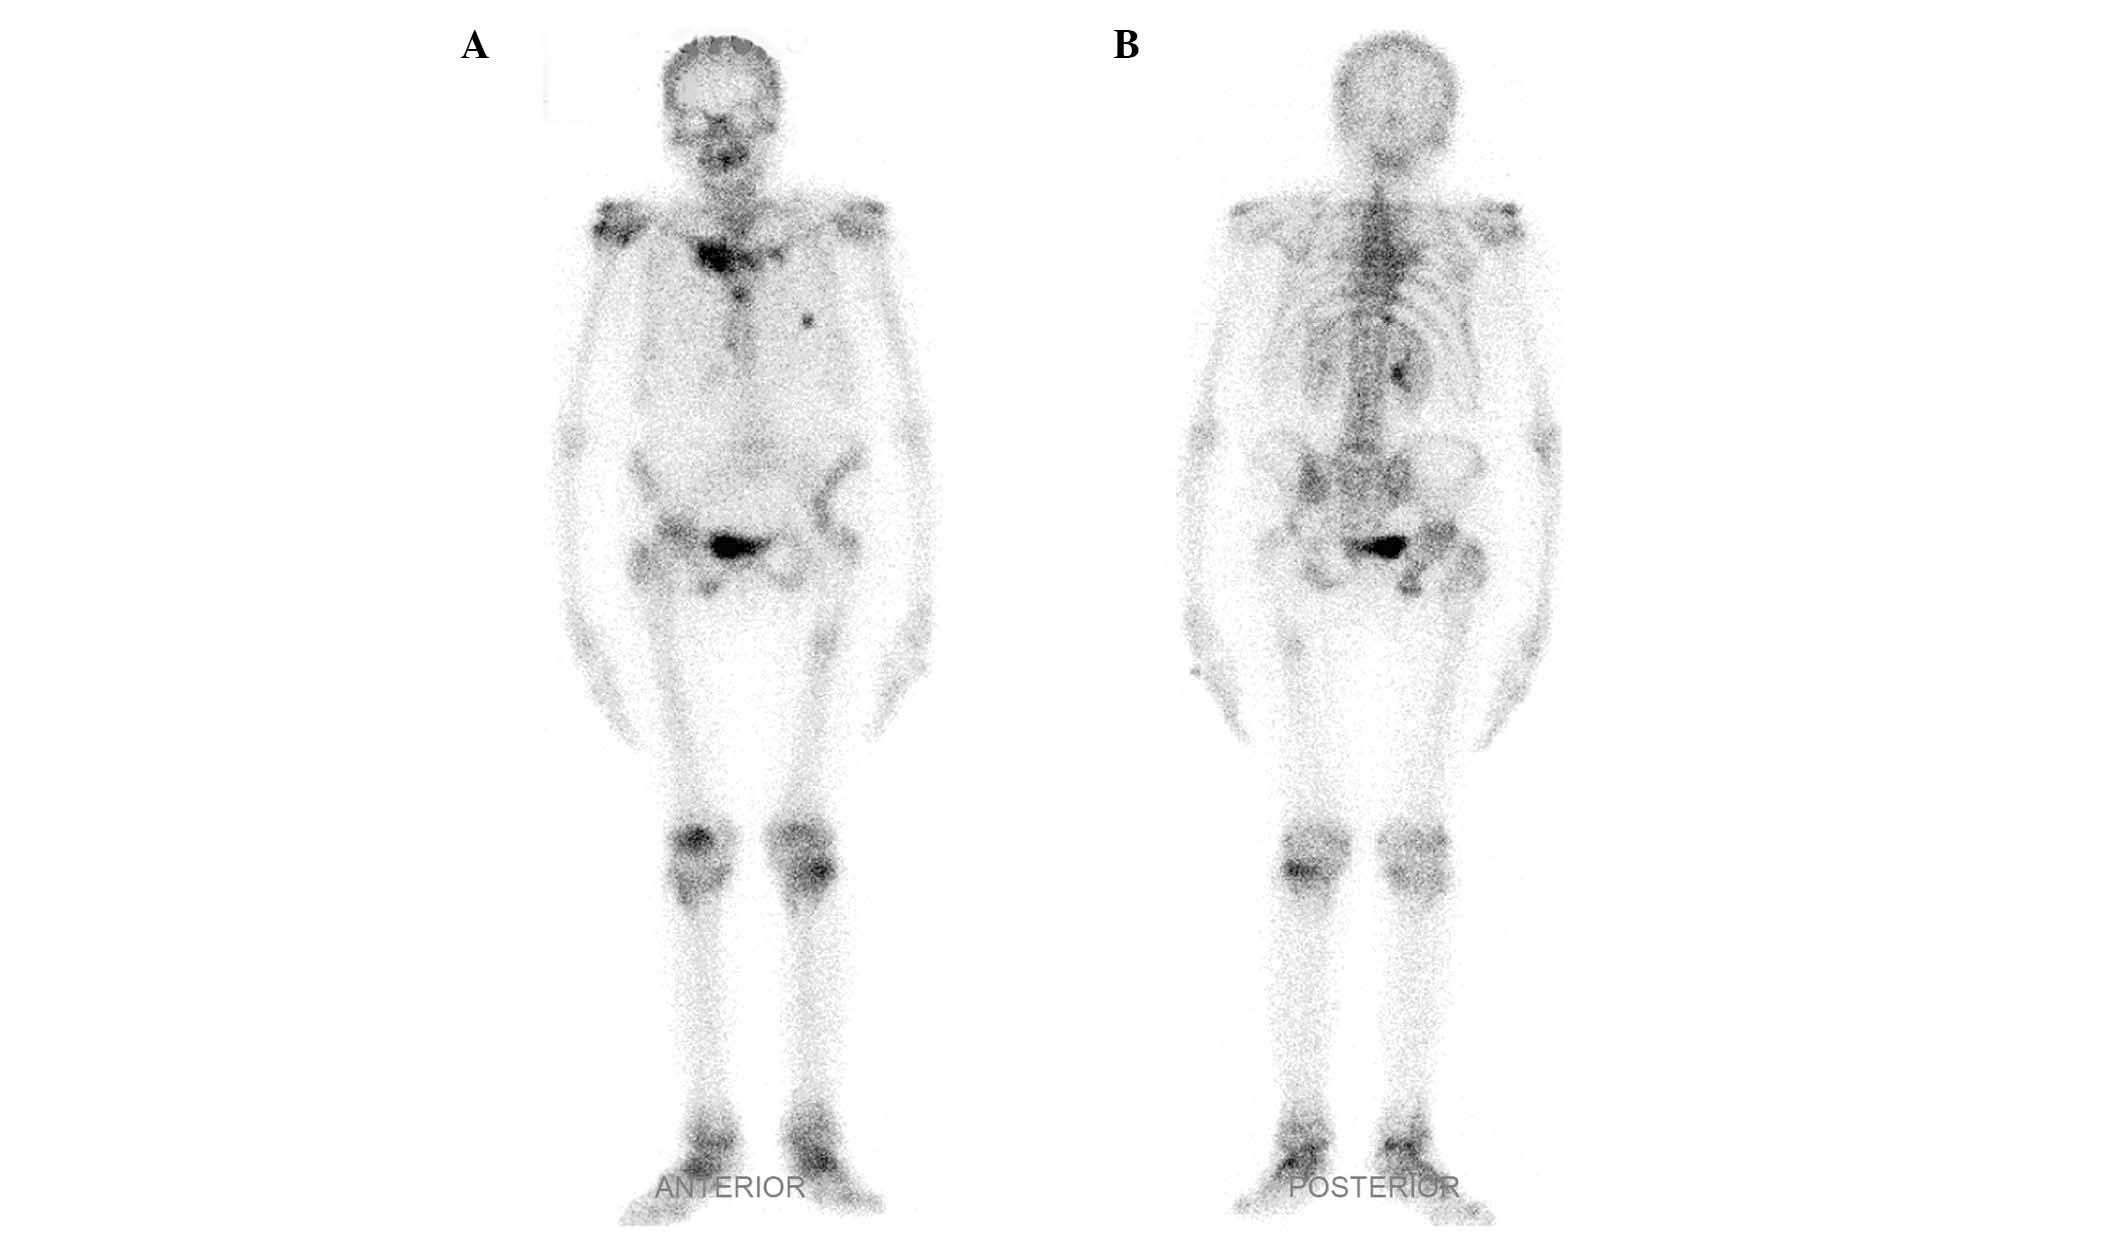

Whole-body 99m Tc methylene diphosphonate bone scintigram demonstrates increased uptake in both sternoclavicular joints the sternum the right greater trochanter. These diseases share some clinical radiologic and pathologic characteristics. It is composed of two portions separated by an articular disc of fibrocartilageThe bone areas entering into its formation are the sternal end of.

The sternoclavicular joint or sternoclavicular articulation is the joint between the manubrium of the sternum and the clavicle boneIt is structurally classed as a synovial saddle joint and functionally classed as a diarthrosis and multiaxial joint. B Bone scintigram obtained with technetium 99m 99m Tc medronate shows areas of increased radiotracer activity in the medial aspect of both clavicles arrows and in the. An entity initially known as chronic recurrent multifocal osteomyelitis was first described in 1972.